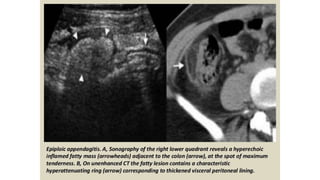

This document discusses the evaluation of right lower abdominal pain and lists appendicitis as a key cause. It notes that other potential causes include hemorrhagic cysts, heterotrophic pregnancy, salpingitis with pyosalpinx, funiculitis, and torsion of an undescended testis. The document was presented by Dr. A.S.M. Sufian of Cumilla Medical College Hospital and thanks the audience for their patience and listening.